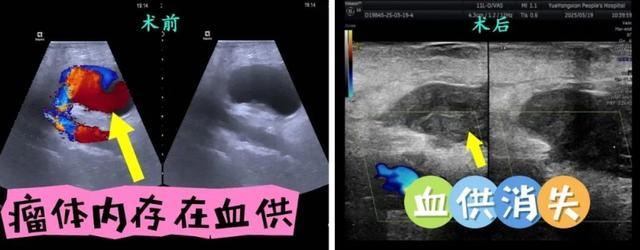

术前B超发现肿块持续变大已达72*29mm(似拳头大小),瘤颈处约达9.2mm。手术在超声实时引导下,经皮穿刺进入假性动脉瘤腔,连接装有适量凝血酶溶液的注射器,缓慢匀速向瘤腔内注入凝血酶,B超影像中可见瘤腔内血流信号逐渐减弱直至消失。术中患者生命体征平稳,无任何不良反应。术后患者右腹股沟疼痛消失,治疗效果明显。